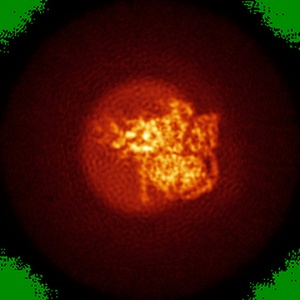

Cryo-EM structure of parathyroid hormone receptor type 1 in complex with a long-acting parathyroid hormone analog and G protein

Single-particle4.0 Å